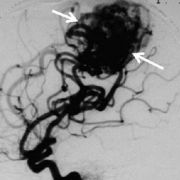

脑动静脉畸形 (AVMs)是一种少见的脑血管病变,其特征是大量异常扩张的动静脉和直接动静脉分流。它们通常在青年期发现,并可伴有头痛、癫痫,或较常见的颅内出血,后者可导致...

问:妊娠和产褥期会增加脑动静脉畸形破裂的风险吗? 答:研究表明妊娠和产褥期脑动静脉畸形患者未发现出血风险增加。因此,我们不建议患有颅内AVM的女性避免怀孕。 脑动静脉畸...

问: 脑动静脉畸形 都是在什么情况下破裂的? 答:脑动静脉畸形是先天性的,是畸形的动脉和静脉簇彼此直接相连。由于它是先天性畸形,医生不知道它会多久破裂。 脑动静脉畸形都...